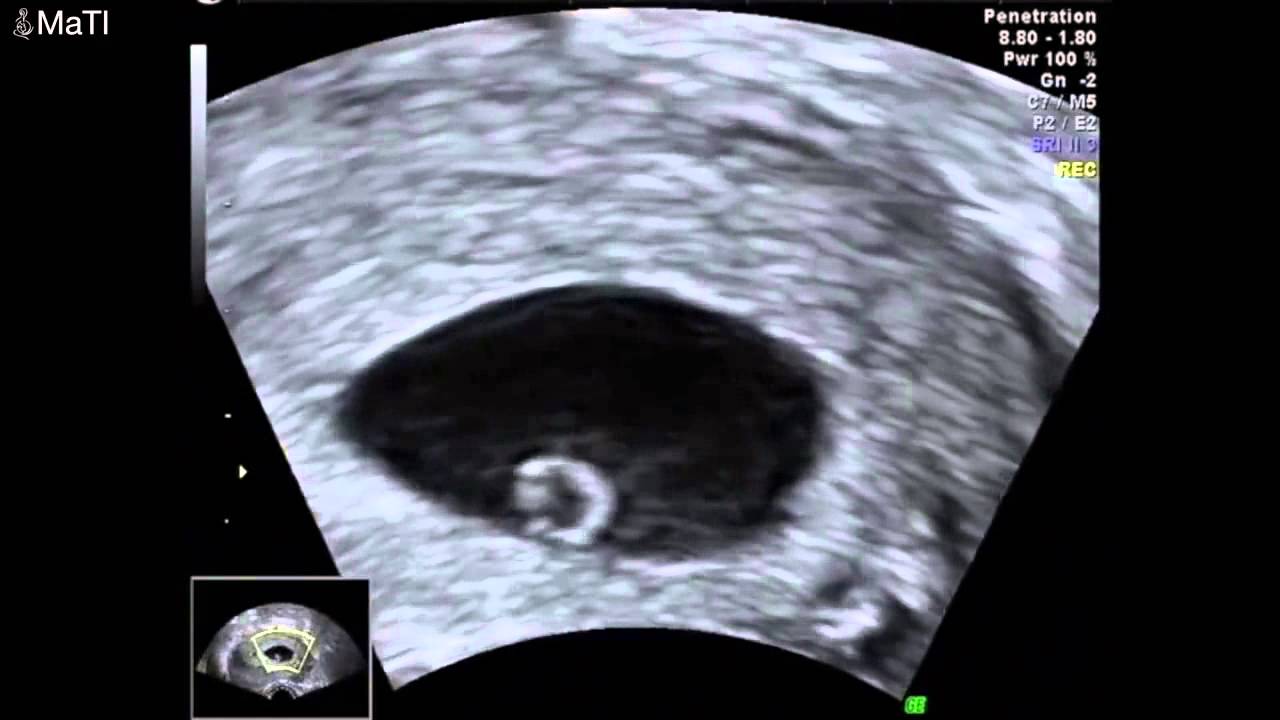

Bebeğin ileride kol ve bacaklarını oluşturacak tomurcuklar şimdiden belirginleşmeye başlar. Bebeğin kalbi bu dönemde vücudun büyük çoğunluğunu kapsar. 7 haftalik gebeli̇k (hami̇leli̇k) görüntüsü. Hamilelik macerasının ilk ayları olan 6 haftalık gebelik, bazı kadınlar için hamilelik müjdesinin yeni alındığı, kimi kadınlar içinse heyecanların yeni başladığı bir dönemdir.hamilelik teşhisi konulmuş ise, gidilen ultrason muayenesinde bebeğin kalp atışları bu hafta içinde rahatlıkla duyulabilir. 6 haftalık gebelikte bebeğin ultrason görüntüsü gebelikte 6 haftalık bebek görüntüsü. Ultrason, 6 ile 8 haftadan sonra çoğul gebeliği anlamak için hatasız sonuçlar verir. 6 haftalık ultrason görüntüsü erken gebelik belirtileri (merhaba, sabah bulantısı !) tam etkilerini hissediyor olabilirsiniz, ancak iyi haber şu ki, yakında bebeğinizin yüzü. Hamileliğini öğrenen anneler, ultrasonda bebeğini görmek için büyük bir istek duyabilir. Bebeğin ileride kol ve bacaklarını oluşturacak tomurcuklar şimdiden belirginleşmeye başlar.

Hamileliğini öğrenen anneler, ultrasonda bebeğini görmek için büyük bir istek duyabilir. Beyin, omurga, büyük damarlar, göz ve barsak, böbrek, karaciğer gibi organlar gelişmeye başlamıştır. Altı haftalık gebelikte bebeğin kalp atışları rahatlıkla ultrason muayenesinde duyulabilir ve görülebilir. Evet, 6 haftalık hamilelikte doktorunuz gebelik kesesi içinde bebeğe ait kabartıyı görebilir. Haftasında bebeğin başı ile vücudunun kalan kısmı yaklaşık aynı büyüklükte görünmektedir. Bebeğinizin kalbi 2 mm boyutuna ulaşmış ve aktif bir şekilde çalışıyordur.

Bu döneme kadar temel haliyle oluşmuş olan dolaşım sistemi artık bebeğinizin kalbine kan pompalamaya başlar. Bebeğin beyni gelişmeye ve aktivite göstermeye başlamıştır. 6 haftalık gebelikle beraber anne karnındaki bebekte çeşitli değişimler meydana gelir. Gebelik testi pozitif çıkan kadınlarda 5 veya 6. Hafta arka kısım ön bölgeden daha hızlı gelişim. Eğer doğurganlık tedavileriyle hamile kaldıysanız, aşılanan embriyoların sayısını görmek için daha erken, yani yaklaşık ilk 8 hafta içinde ultrasona alınırsınız.

Eğer doğurganlık tedavileriyle hamile kaldıysanız, aşılanan embriyoların sayısını görmek için daha erken, yani yaklaşık ilk 8 hafta içinde ultrasona alınırsınız. Bebeğin beyni gelişmeye ve aktivite göstermeye başlamıştır. 6 haftalık gebelik kesesi ultrason görüntüsü 6 haftalık gebelik belirtileri. 6 haftalık gebelik kesesi bazen görülmeyebilir, bu durumda vajinal ultrason muayenesi yapılabilir. 6 haftalık gebelikte ultrason görüntüsü, her ne kadar yalnızca küçük bir noktadan oluşsa da gebelik hakkında çok önemli bilgiler verir. 6 haftalık bebek ultrason görüntüsü.

6 haftalık ultrason görüntülerinde (6 haftalık bebek görüntüsü anne karnında) bebeğin resminden pek birşey anlamayabiliriniz ancak aşağıdaki resimde bebeğin başından en ucuna giden kıvrımlı bir yapı göreceksiniz. Genel olarak 6 haftalık görüntülerde bebeğin vücut siması, akciğeri, oldukça minik el yapısı da görülmeye başlanabilir. Hafta bitimindeki kontrolünüzde gebelik keseniz ultrasonda kesin olarak görünecek hatta kesenin içerisinde, ileride bebeğiniz olarak kucağınıza alacağınız canın yavaş yavaş.

Bu hafta bebek kese içinde çok küçük bir nokta olarak görülebilir. Bu döneme kadar temel haliyle oluşmuş olan dolaşım sistemi artık bebeğinizin kalbine kan pompalamaya başlar. Gebelik testi pozitif çıkan kadınlarda 5 veya 6.

Bu haftada embriyonun organlarının çoğunun oluşumu başlar, bu nedenle bebeğin. Anne adayları tarafından sıklıkla merak edilen sorulardan biri 6 haftalık bebek kaç mm olur şeklindedir. 6 haftalık bebek görüntüsü 6 haftalık bebek ultrason görüntüsü embriyonun 3 ila 5 mm boyutlarında olduğu bilgisini edinmenize olanak tanır.

6 haftalık bebek ultrason görüntüsü. Hamilelik macerasının ilk ayları olan 6 haftalık gebelik, bazı kadınlar için hamilelik müjdesinin yeni alındığı, kimi kadınlar içinse heyecanların yeni başladığı bir dönemdir.hamilelik teşhisi konulmuş ise, gidilen ultrason muayenesinde bebeğin kalp atışları bu hafta içinde rahatlıkla duyulabilir. Bu hafta bebek kese içinde çok küçük bir nokta olarak görülebilir.

6 haftalık gebelikte bebeğin ultrason görüntüsü üst resimdeki gibidir. Haftası nda ultason ile bebeğinizin görüntüsünü görebilir, kalp atış sesini duyabilirsiniz. Altı haftalık gebelikte bebeğin kalp atışları rahatlıkla ultrason muayenesinde duyulabilir ve görülebilir.

6 haftalık bebek görüntüsü 6 haftalık bebek ultrason görüntüsü embriyonun 3 ila 5 mm boyutlarında olduğu bilgisini edinmenize olanak tanır. 6 haftalık gebelikte bebek gelişimi ile ilgili olarak gözler oluşmaya başlar ve kolların ve bacakların ana hatları belirir; Bebeğin solunum ve sindirim sistemini oluşturacak ilk yapılar belirginleşir.

6 haftalık gebelik ultrason görüntüsü nasıldır? Gebeliğin altıncı haftasında hızla büyümeye devam eden bebeğin anne karnındaki görüntüsü netleşmeye başlar. Eğer doğurganlık tedavileriyle hamile kaldıysanız, aşılanan embriyoların sayısını görmek için daha erken, yani yaklaşık ilk 8 hafta içinde ultrasona alınırsınız.

Haftasında bebeğin başı ile vücudunun kalan kısmı yaklaşık aynı büyüklükte görünmektedir. 6 haftalık gebelikte ultrason görüntüsü, her ne kadar yalnızca küçük bir noktadan oluşsa da gebelik hakkında çok önemli bilgiler verir. Bebeğin beyni gelişmeye ve aktivite göstermeye başlamıştır.